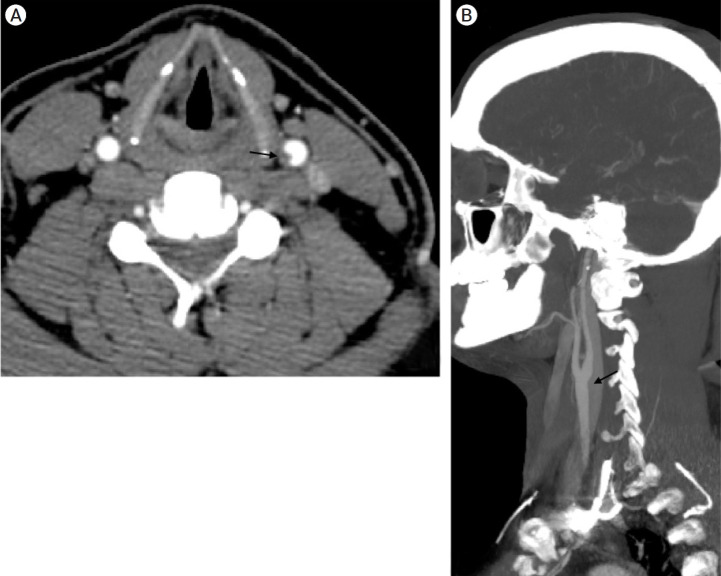

The carotid web (CW), an intimal variant of fibromuscular dysplasia (FMD), is recognized as a cause of stroke and with a high-risk of stroke recurrence. Other names are carotid-bulb atypical FMD, carotid (bulb) diaphragms and it is described like a shelf of tissue from the posterior wall of the carotid bulb. Here we present a case of a young patient with recurrent stroke, with no other risk factors that was diagnosed with a common CW.